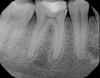

Fig 4. Case 1: Periapical imaging of the maxillary right (Fig 2) and mandibular right (Fig 3) quadrants initially showed no obvious pathology, aside from the horizontally impacted tooth No. 32. Secondary imaging following successful relief of pain after administration of an inferior alveolar nerve block revealed pre-eruptive intracoronal resorption in tooth No. 32 with resultant symptomatic irreversible pulpitis as the likely source of pain (Fig 4).

Figure 4

Although the patient's chief complaint was consistent with a degenerative pulpitis, the clinical and radiographic examination was initially unremarkable. All teeth in the maxillary and mandibular right quadrants were normally responsive to pulp sensitivity testing, and they were neither percussion nor palpation sensitive. Neither swelling nor sinus tracts were present, and the periodontal examination revealed normal probing depths and lack of mobility throughout the quadrant. Initial periapical radiographs revealed normal PDL spaces surrounding teeth Nos. 30 and 31, as well as a horizontally impacted No. 32 with a radiolucency within the crown in close proximity to the distal root surface of No. 31 (Figure 2 and Figure 3). Because the reported pain was severe, and in an effort to not only diagnose the issue but also offer some respite from the severe pain the patient was experiencing, an inferior alveolar nerve block was administered using 3.4 cc 0.5% bupivacaine with 1:200,000 epinephrine. Within 5 minutes of administration, the patient reported complete resolution of his pain.

Given the confirmation of a likely odontogenic source of pathology since pain was relieved by the block anesthesia, secondary periapical imaging was taken, which showed intracoronal resorption in the unerupted tooth No. 32 (Figure 4). Because of the visualizable pathology and signs and symptoms consistent with a symptomatic irreversible pulpitis, the patient was referred to an oral and maxillofacial surgeon for extraction of tooth No. 32. The patient reported complete resolution of symptoms following extraction of the affected tooth. Communication from the oral surgeon confirmed the diagnosis of intracoronal resorption on tooth No. 32.